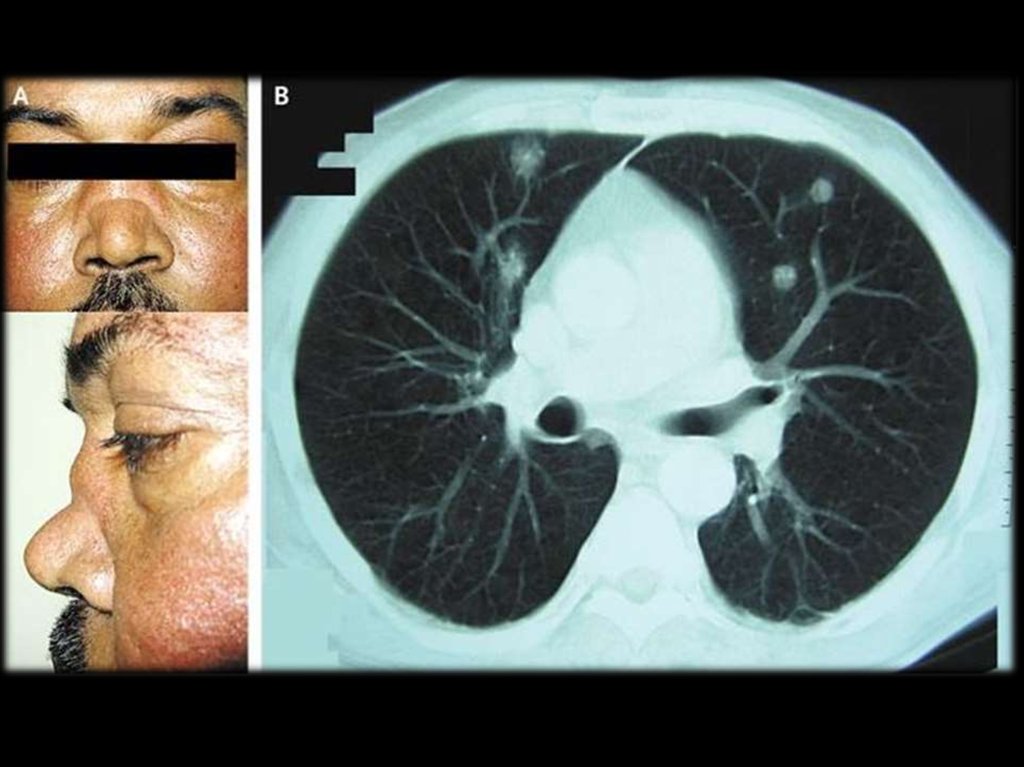

4. Клиника

Болезнь обычно начинается постепенно с

симптомами поражения верхних дыхательных

путей: ринит и синусит, насморк с гнойнокровянистыми

выделениями

из

носа,

заложенность носа, носовые кровотечения,

отсутствие обоняния, сухие корки.

Возможны боли в ухе и значительное снижение

слуха.

При прогрессировании процесса развиваются

язвенно-некротические изменения слизистых

оболочек с вовлечением глотки, гортани,

трахеи:

боль

в

горле,

охриплость,

стридорозное дыхание.

Возможен язвенный стоматит, глоссит, хейлит.

5.

Гранулематозные

синуситы

осложняются

вторичной

инфекцией.

часто

гнойной

Возможно разрушение хряща и костной

ткани

носовой

перегородки,

верхнечелюстной пазухи и орбиты с

формированием

“седловидного

носа”,

выбухание глазного яблока вперёд и вниз

(проптоз), деструкция тканей орбиты и

глазного яблока.

1. воспаление носа и полости рта: язвы в полости

рта, гнойные или кровянистые выделения из

носа;